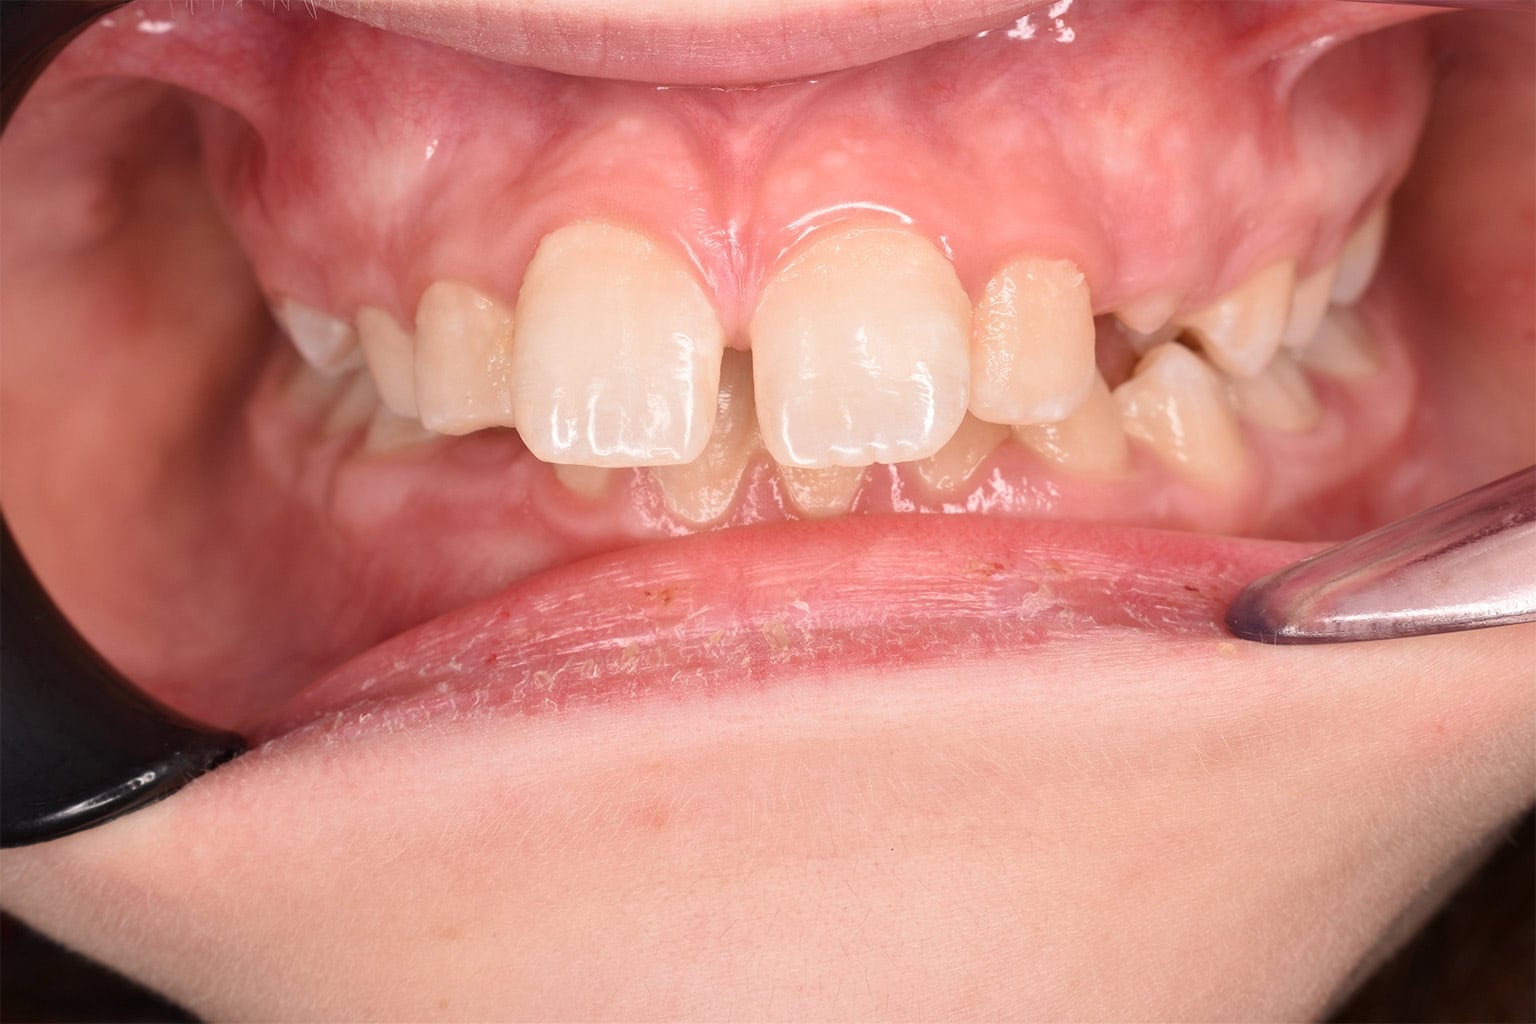

Vorher-Nachher-Ergebnisse

Echte Ergebnisse. Echte Menschen.

Jede Behandlung bei TIEFBLAU Kieferorthopädie ist so individuell wie der Mensch dahinter. In unserer Vorher-Nachher-Galerie zeigen wir Ihnen echte Behandlungsergebnisse aus unserer Praxis in der Kölner Südstadt: Schonend erzielt, präzise geplant und mit dem Anspruch, den wir seit über 40 Jahren an jede Behandlung stellen.

Die Bilder geben Ihnen einen Eindruck davon, was moderne Kieferorthopädie leisten kann, ob bei Kindern, Jugendlichen oder Erwachsenen.

Der sichtbare Unterschied

Dokumentiert. Überzeugend. Nachhaltig.